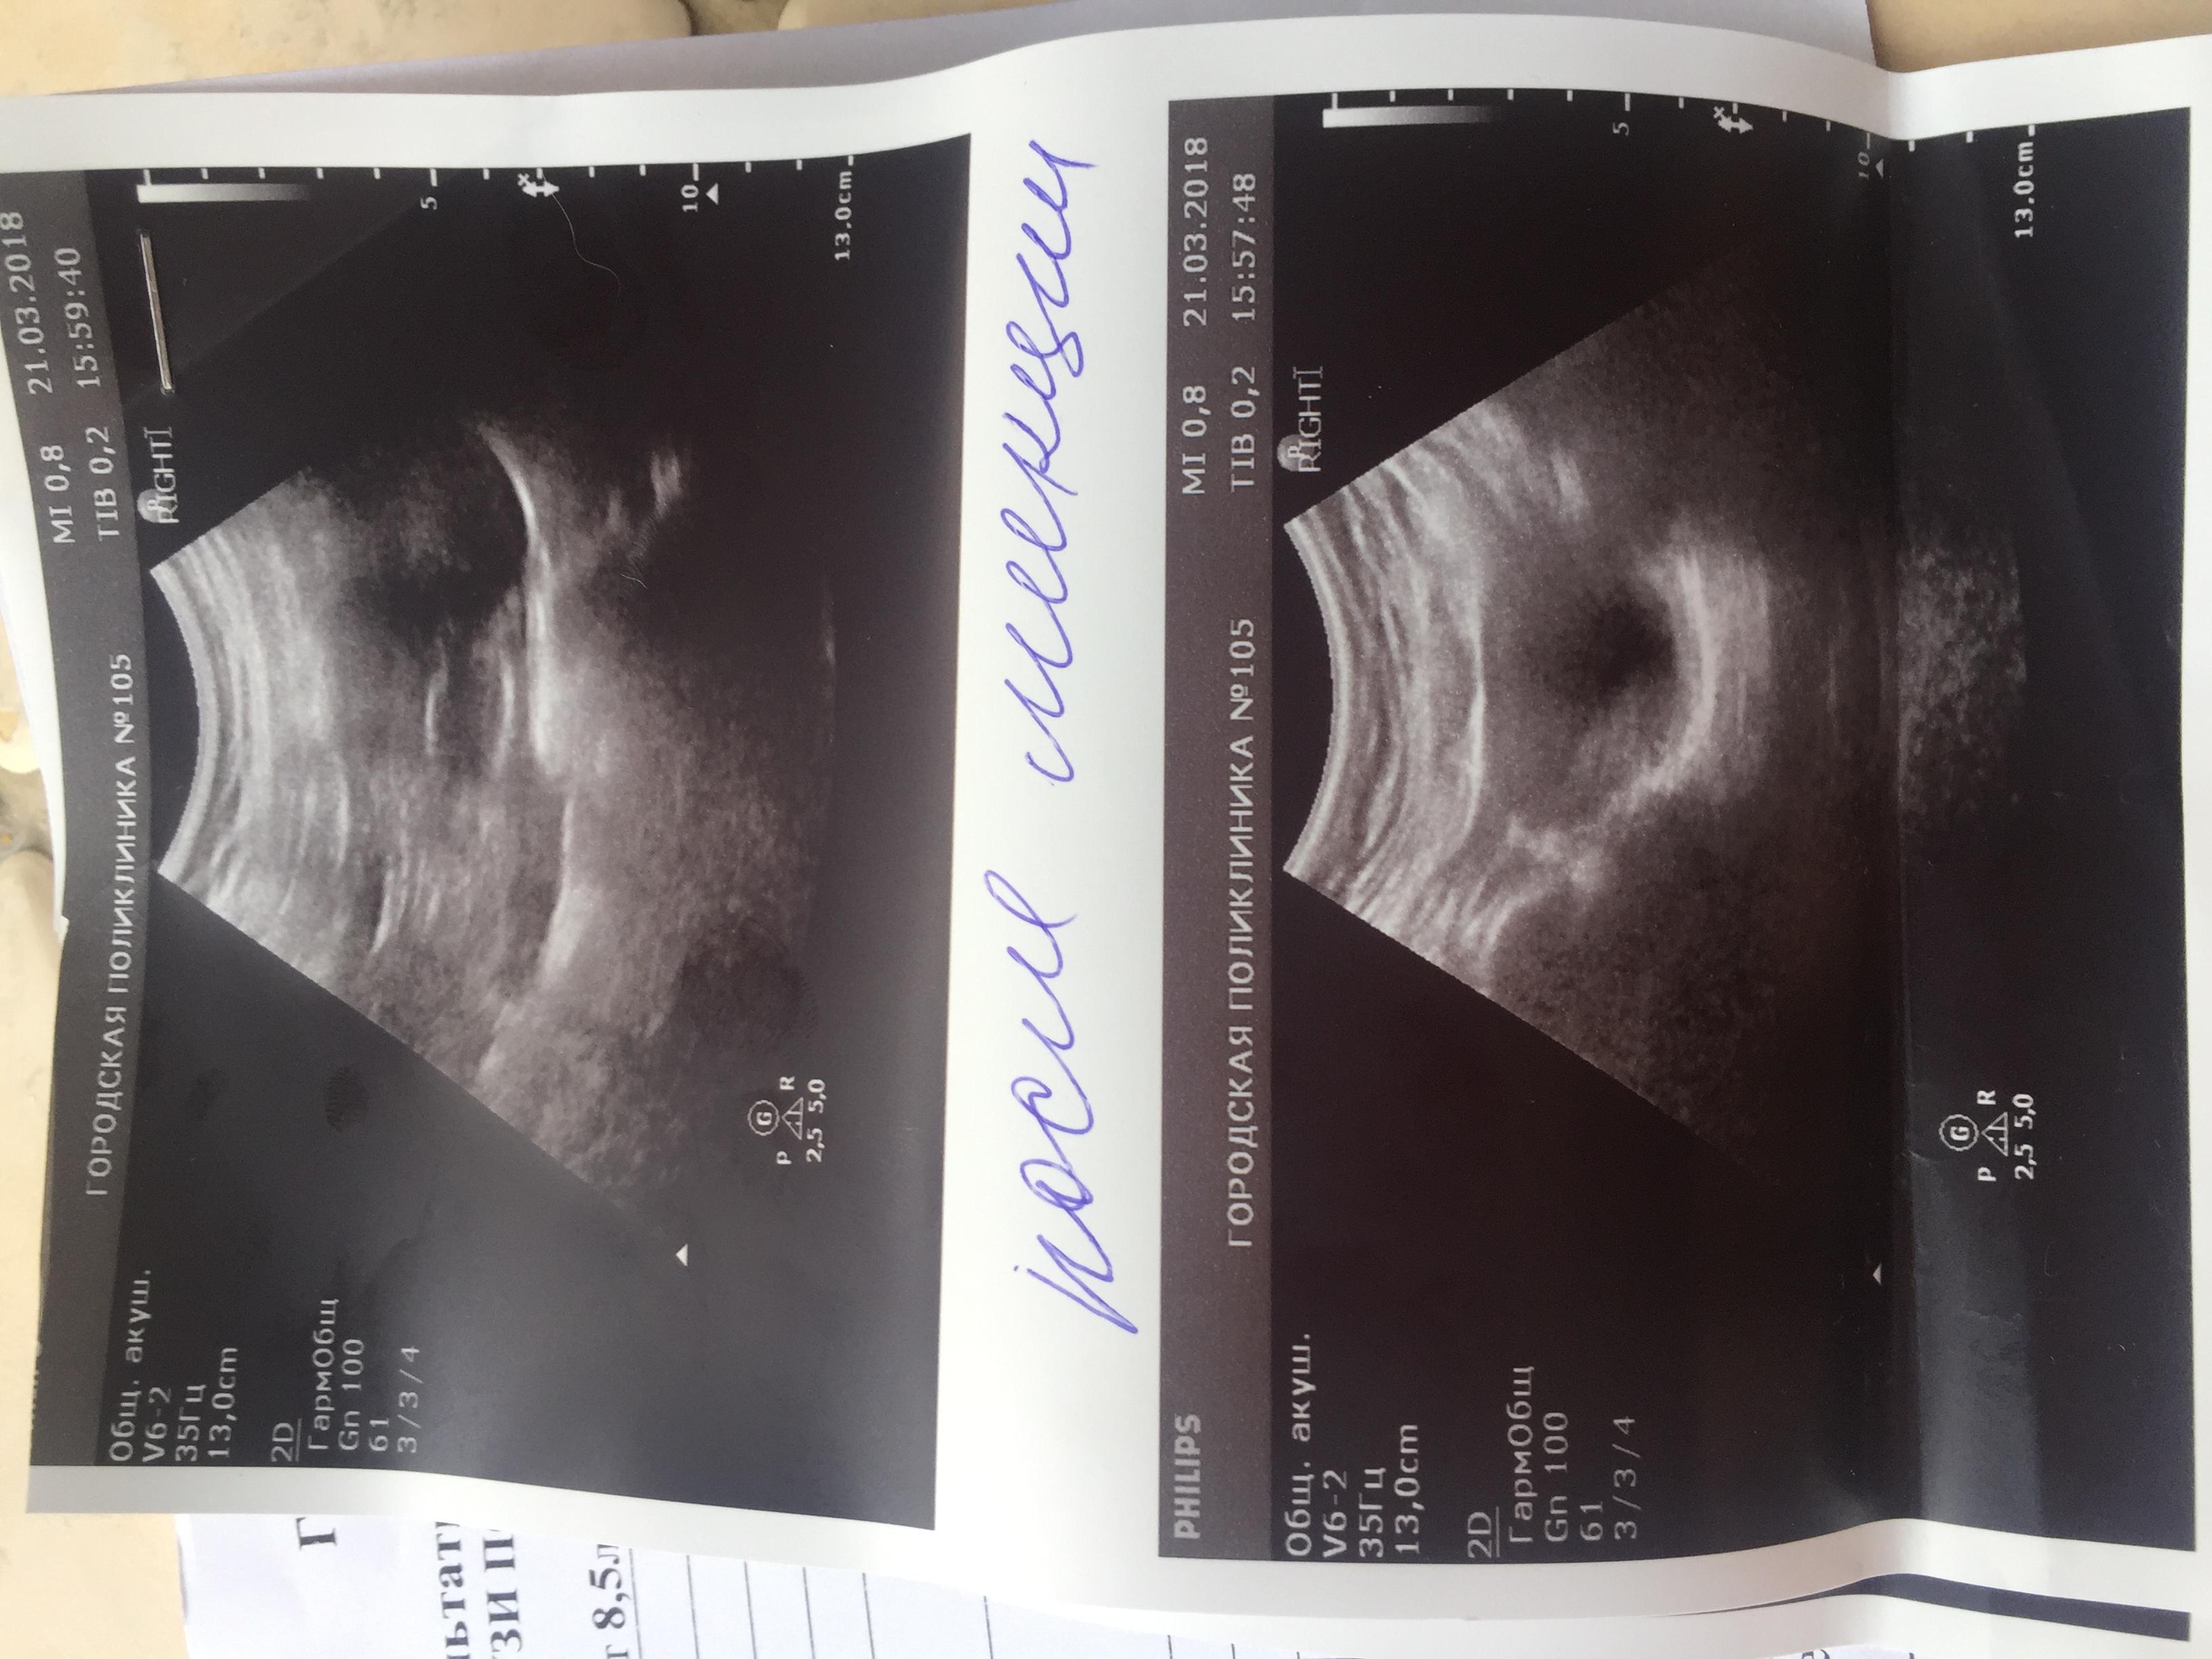

Здравствуйте. С Рождения гидронефроз левой почки , была удалена в декабре 2009 года. Анализы мочи и биохим анализ крови все показатели всегда в норме. Ребёнку 8 лет, сейчас одно УЗИ показывает размер почки 112 на 56, лоханка 16 мм. Другое узи сделанное через день показало: размер почки 78 на 30 , лоханка 7 мм. Паренхима на обоих узи 13 мм. Так же было сделано исследование УЗДГ почки ( все в норме, отклонений нет) Не можем понять почему такая разница по УЗИ где правда ? Как нам с этим разобраться .